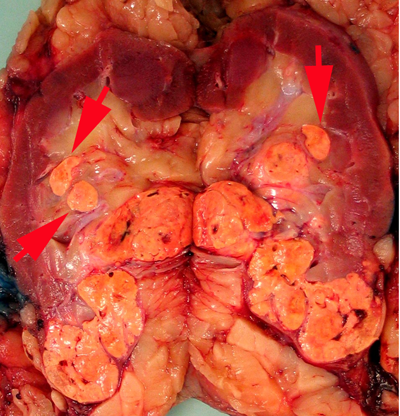

Sampling tumor

Previous sampling recommendations have been to take at least one block/cm of greatest dimension of tumor (26, 28). Areas of different appearance or consistency and blocks to demonstrate tumor relationship with peri-renal fat, renal sinus, renal pelvis and adrenal gland should also be taken. There was consensus that sampling should follow this general guideline of sampling with a minimum of three blocks. Multiple tumors are commonly found in hereditary syndromes such as von Hippel-Lindau disease, hereditary papillary RCC, Tuberous sclerosis and Birt-Hogg-Dube syndrome (29-31). Multiple tumors also occur with oncocytosis, acquired cystic kidney disease and with papillary RCC (32, 33). Multifocality in sporadic RCC is rare. It is extremely uncommon to have >5 tumors in one kidney and in such instances sampling issues are not addressed in the literature. There was consensus that in cases with multiple tumors, sampling should include the 5 largest tumors at a minimum.

Sampling the renal sinus

The renal sinus is the fatty tissue compartment that lies between renal parenchyma and the pelvi-calyceal system. This is a complex structure with the vascular system being anterior to the pelvi-calyceal system and the sinus extending anteriorly and posteriorly within the kidney (7). Veins entering the renal sinus have a smooth muscle media of variable thickness. Gross recognition of renal sinus involvement is often not difficult and rounded nodules in the renal sinus outside the main tumor indicate sinus vein invasion (Fig. 1A).